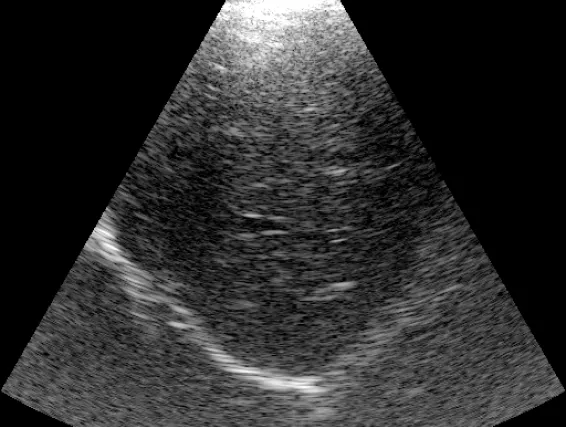

Identifier et quantifier un syndrome interstitiel diffus. Bien qu'évocateur d'un œdème pulmonaire aigu (OAP) en contexte d'urgence, ce signe doit être confronté à la clinique pour écarter les autres étiologies (pneumopathie, fibrose, SDRA...).

Points clés

- Reconnaissance des artefacts en "queue de comète" (lignes B) : verticaux, partant de la ligne pleurale.

- Quantification : Présence de multiples lignes B (> 3) par champ, comme illustré sur l'image.

- Identification des formes sévères : Lignes B coalescentes (aspect de "poumon blanc") et effacement des lignes A.